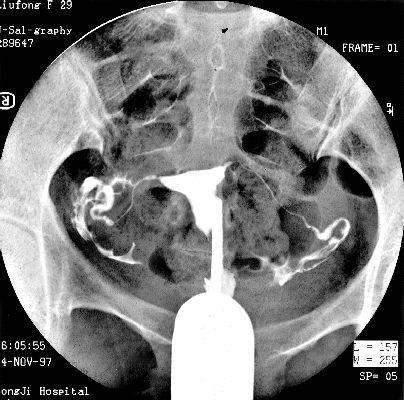

照片名称:子宫输卵管造影3

照片名称:子宫输卵管造影4